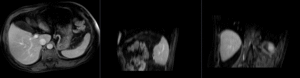

insufficient mask: nonrigid registered with liver mask only, note the misalignment in the remaining abdomen

Color overlay of registered MRI onto CT, illustrating the fusion: MRI soft tissue contrast shows substructures & vasculature invisible on the CT